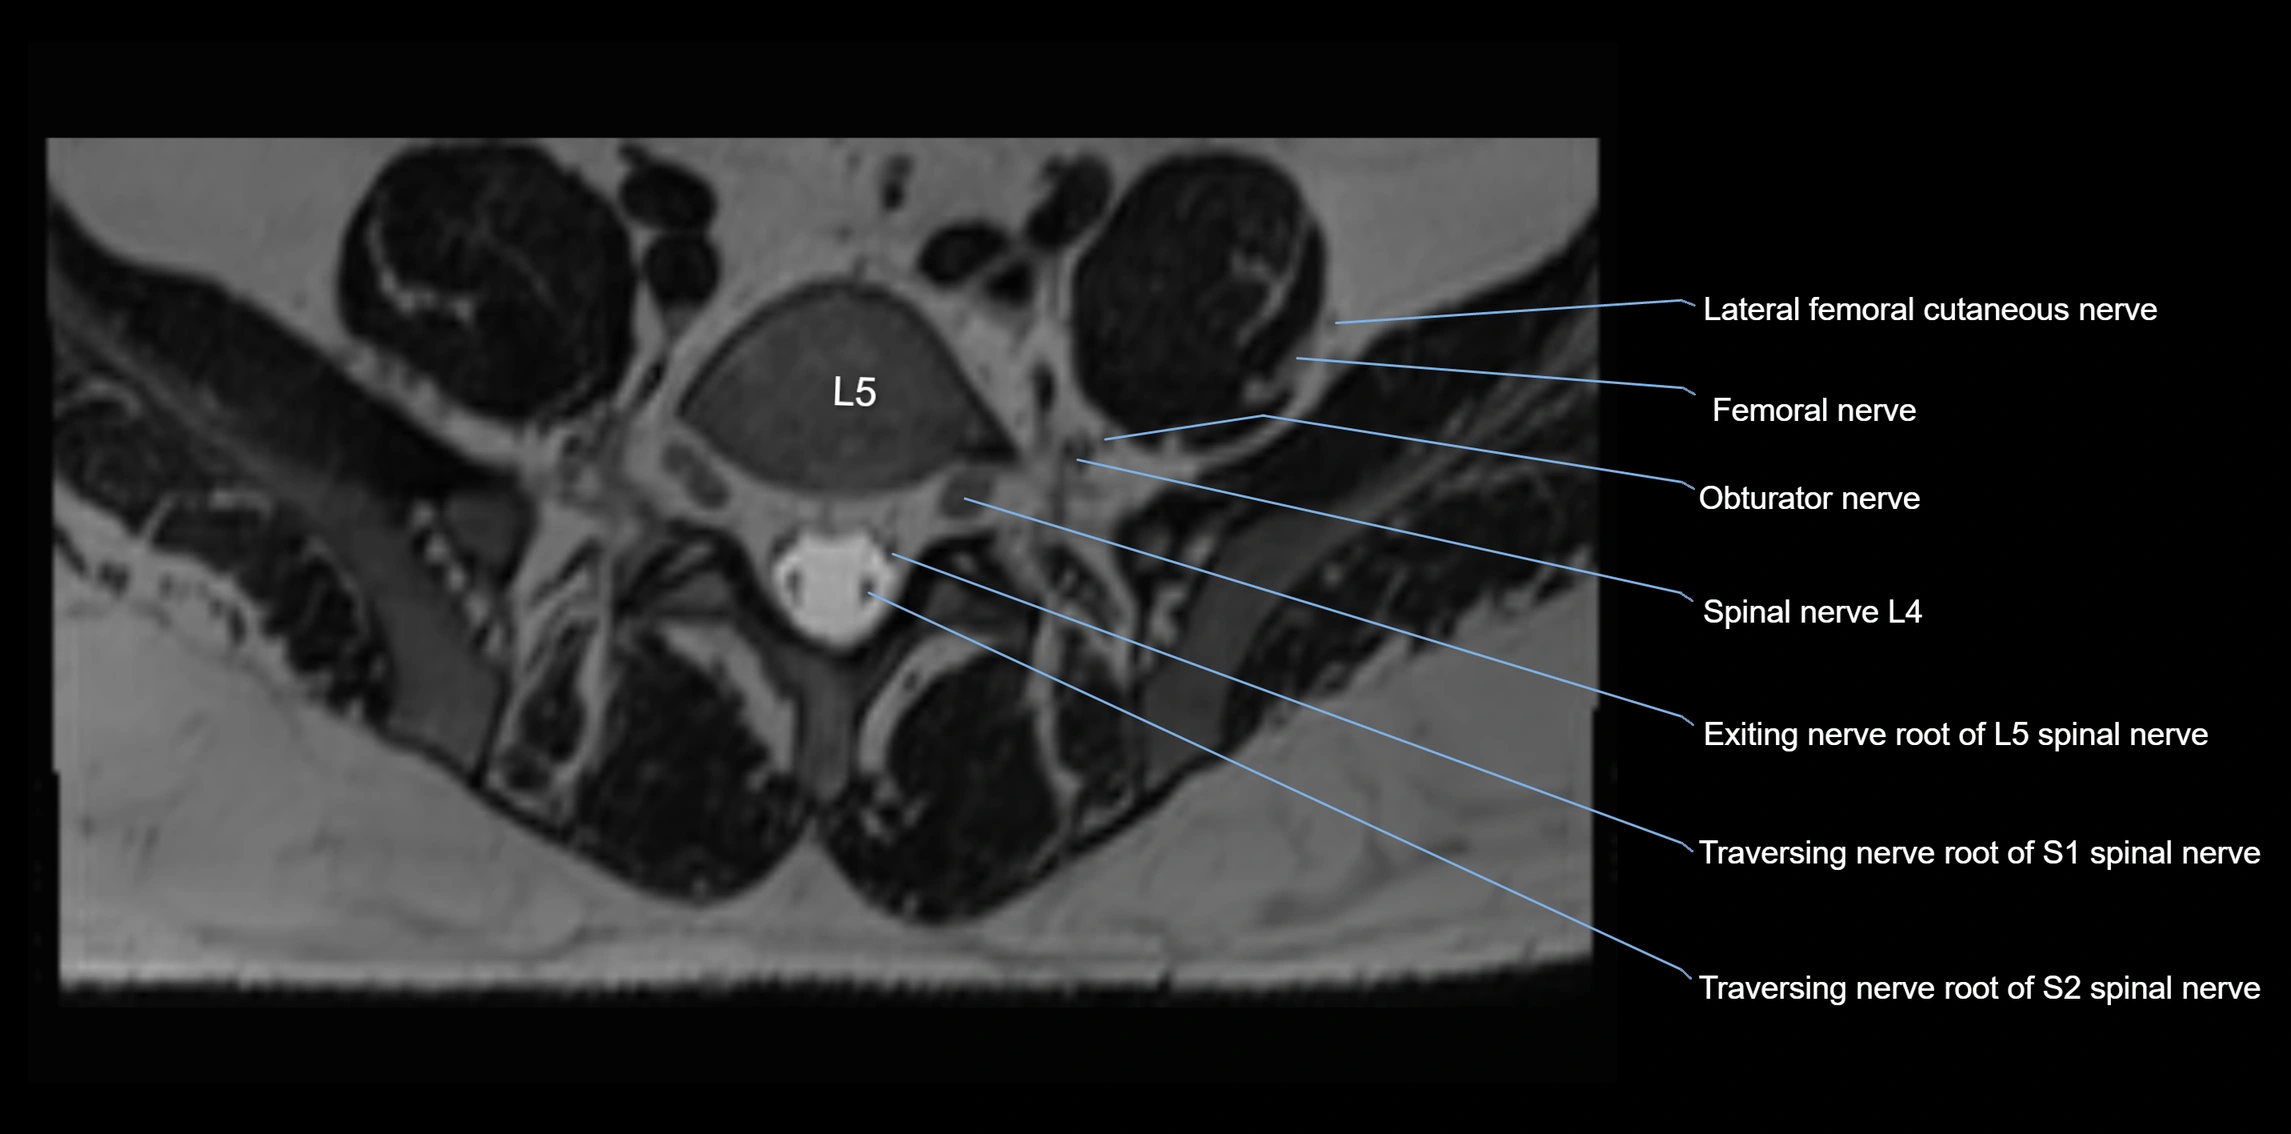

MRI Appearance

T1-weighted images:

• Nerve appears as a very thin low-to-intermediate signal intensity structure

• Surrounded by bright fat, aiding visualization

T2-weighted images:

• Nerve shows intermediate to mildly hyperintense signal compared to muscle

• Pathological involvement appears brighter

STIR (Short Tau Inversion Recovery):

• Normal nerve appears dark

• Inflamed or entrapped nerve appears bright hyperintense

T1 Fat-Sat Post-Contrast:

• Normal nerve enhances minimally

• Pathologic nerve (neuritis, entrapment, tumor infiltration) shows focal or diffuse enhancement

3D T2 SPACE / CISS:

• Nerve appears intermediate to mildly hyperintense compared to muscle

• Surrounded by bright fat or CSF, improving visualization

• Best sequence for mapping small pelvic nerves such as the anococcygeal